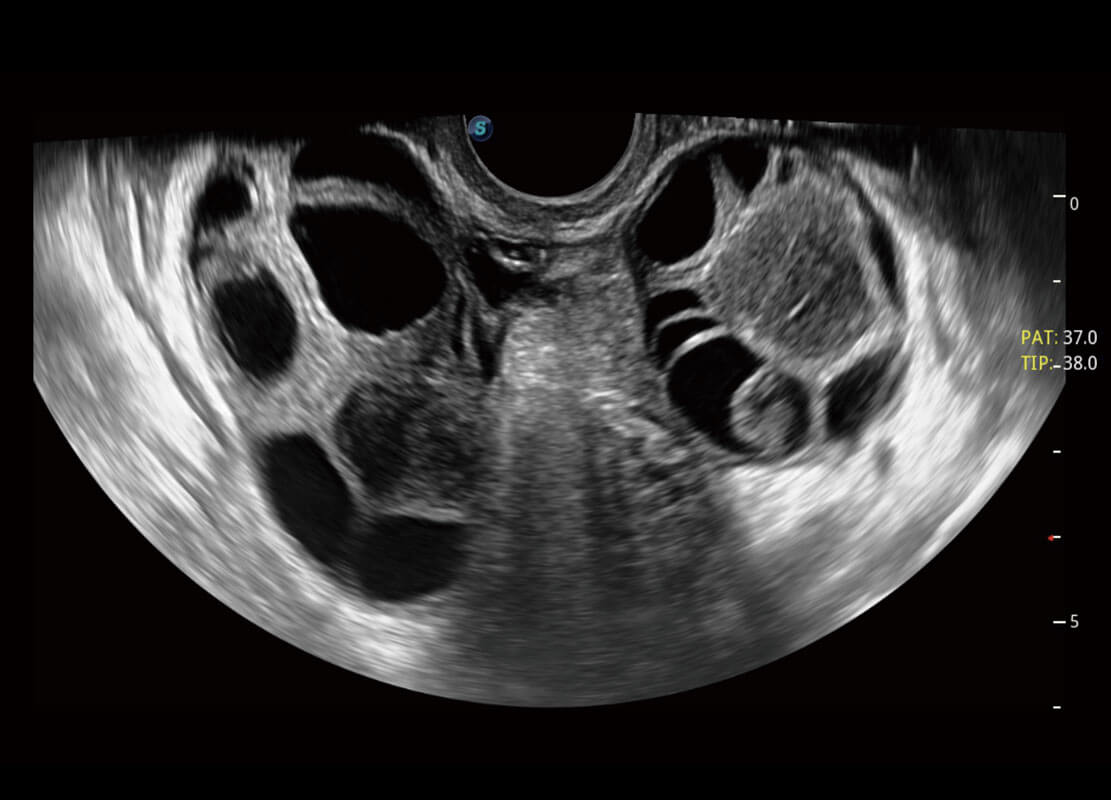

P60优异的图像质量搭载专科探头,在妇科基础疾病的诊断、卵泡生长的监测、输卵管通畅情况的判别等方面为您提供生殖应用方案。

• 腔内妇科-卵巢